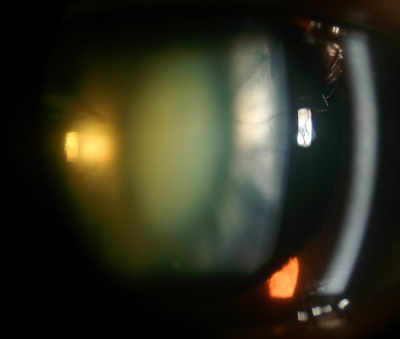

Diabetic Snowflake Cataract

Etiology

Diabetic snowflake cataracts appear as gray-white subcapsular opacities. Often, these cataracts progress rapidly, and the entire lens becomes intumescent and white. Cataracts often occur at younger ages in diabetic patients due to osmotic stress from intracellular accumulation of sorbitol in the lens secondary to elevated intraocular glucose. A rapid-onset form of cataract, which is quite uncommon, may be found in some diabetic patients with very elevated blood sugars, especially younger type 1 diabetics.